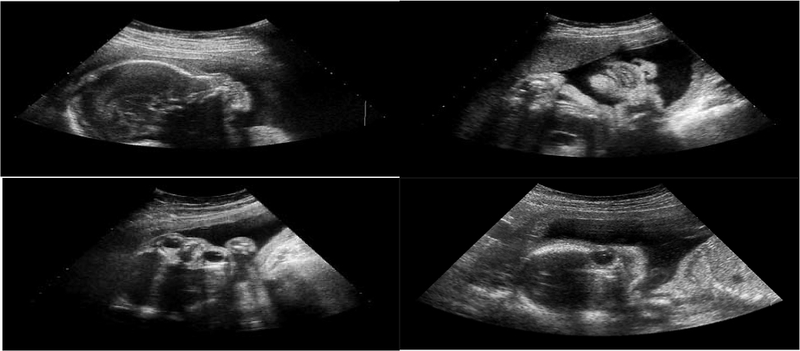

Quá trình thai làm tổ là một giai đoạn quan trọng trong quá trình mang thai, đánh dấu sự bắt đầu của một cuộc sống mới. Vậy thai vào tử cung trong bao lâu? Hãy cùng tìm hiểu qua bài viết tham khảo dưới đây nhé.

Quá trình trứng di chuyển và làm tổ trong buồng tử cung là một hành trình kỳ diệu của sự sống. Sau khi trứng được thụ tinh, nó sẽ bắt đầu một cuộc hành trình tuy ngắn nhưng vô cùng quan trọng để đến và làm tổ trong lòng tử cung.

Thông thường, thai sẽ vào tử cung để làm tổ trong khoảng 6–12 ngày sau khi thụ tinh, muộn nhất là khoảng 2 tuần. Sau khi tinh trùng thụ tinh với trứng trong ống dẫn trứng, trứng đã thụ tinh sẽ di chuyển dần về phía tử cung, đồng thời trải qua quá trình phân chia tế bào. Khi đến tử cung, phôi sẽ bám vào niêm mạc tử cung để làm tổ, đánh dấu sự bắt đầu của thai kỳ ổn định.

Sau khi trứng được thụ tinh và di chuyển qua ống dẫn trứng, phôi sẽ bắt đầu làm tổ trong lòng tử cung. Quá trình này được gọi là làm tổ và thường diễn ra trong khoảng thời gian từ 6 đến 12 ngày sau khi thụ tinh. Khi phôi làm tổ thành công, nó sẽ bắt đầu phát triển và hình thành nhau thai để cung cấp dưỡng chất cho thai nhi. Những yếu tố ảnh hưởng đến quá trình thai vào tử cung bao gồm:

Để xác định chính xác thai đã vào tử cung hay chưa, phương pháp tốt nhất là làm các xét nghiệm y khoa. Các dấu hiệu nhận biết ban đầu như đau bụng, chảy máu nhẹ…, chỉ mang tính chất tham khảo và có thể do nhiều nguyên nhân khác gây ra.